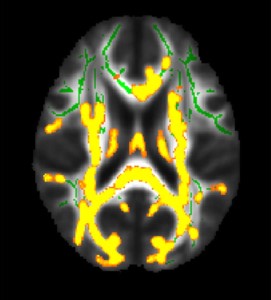

يُظهر الشكل زيادة الالتهاب العصبي (الألوان الصفراء) المرتبط بارتفاع الدهون الحشوية، وتعبر الألوان الخضراء عن المادة البيضاء العادية

ووجد الباحثون أن ارتفاع نسبة الدهون الحشوية كان مرتبطًا بارتفاع امتصاص مادة الأميلويد في المناطق الدماغية المعروفة بتأثرها مبكرًا بتراكم بروتين الأميلويد في مرض ألزهايمر.

وكانت هذه العلاقة أسوأ عند الرجال منها عند النساء، ووجد الباحثون أيضًا أن قياسات الدهون الحشوية المرتفعة ترتبط بزيادة عبء الالتهاب في الدماغ.